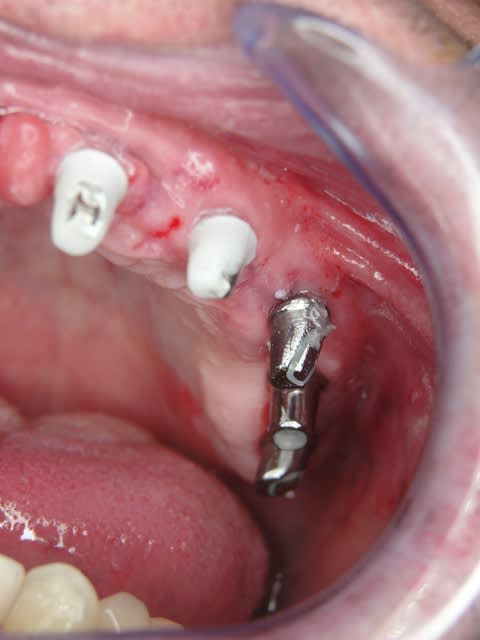

Les deux premières photos montrent le cas d´une jeune femme ( qui malheureusement s est fait retiré toutes les dents à l´étranger....).Ce cas a pu être terminé deux semaines après l´implantation.

Les forets utilisés ont 3 faces et sont coniques (250 trs/min) permettent une condensation de l´os et un traitement minimalement invasif.